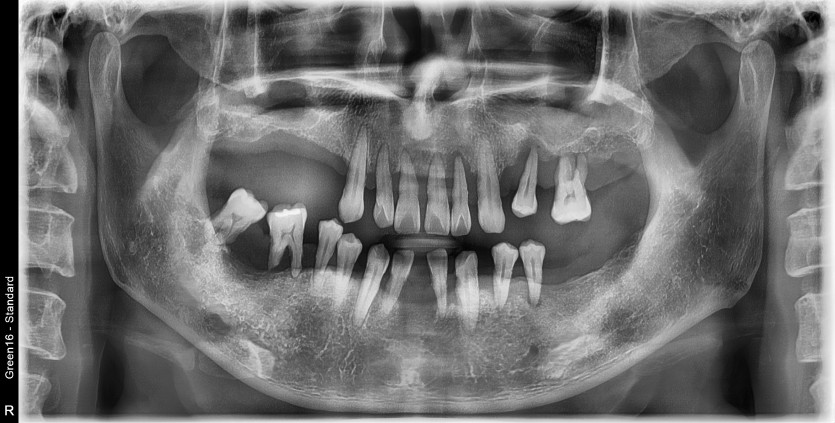

만 49세 전체 임플란트 증례

전체 임플란트 증례입니다.

18개의 임플란트로 완성하였습니다.